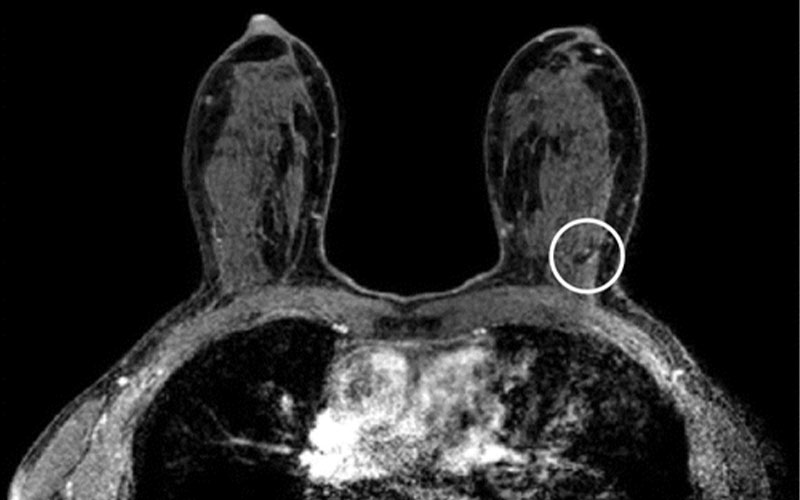

MRI scans in a 54-year-old participant in the second round compared with (c) the MRI scan from the first round (prevalence round). Her current axial post-contrast T1-weighted MRI scan (a) shows a sharply demarcated 3-mm lesion in the left upper outer quadrant (arrow). The lesion shows type 2 kinetics (kinetic overlay not shown) and no diffusion restriction (circled area on b) on the axial apparent diffusion coefficient map (b). In a non–high-risk screening examination, this indifferent focus would normally not be recalled. In this case, the participant was recalled because comparison with her prior axial post-contrast T1-weighted MRI scan (c) revealed that this focus was new (circled area on c). Biopsy showed an infiltrating lobular carcinoma.

Veenhuizen et al, Radiology 2021; 299:278–286; © RSNA 2021